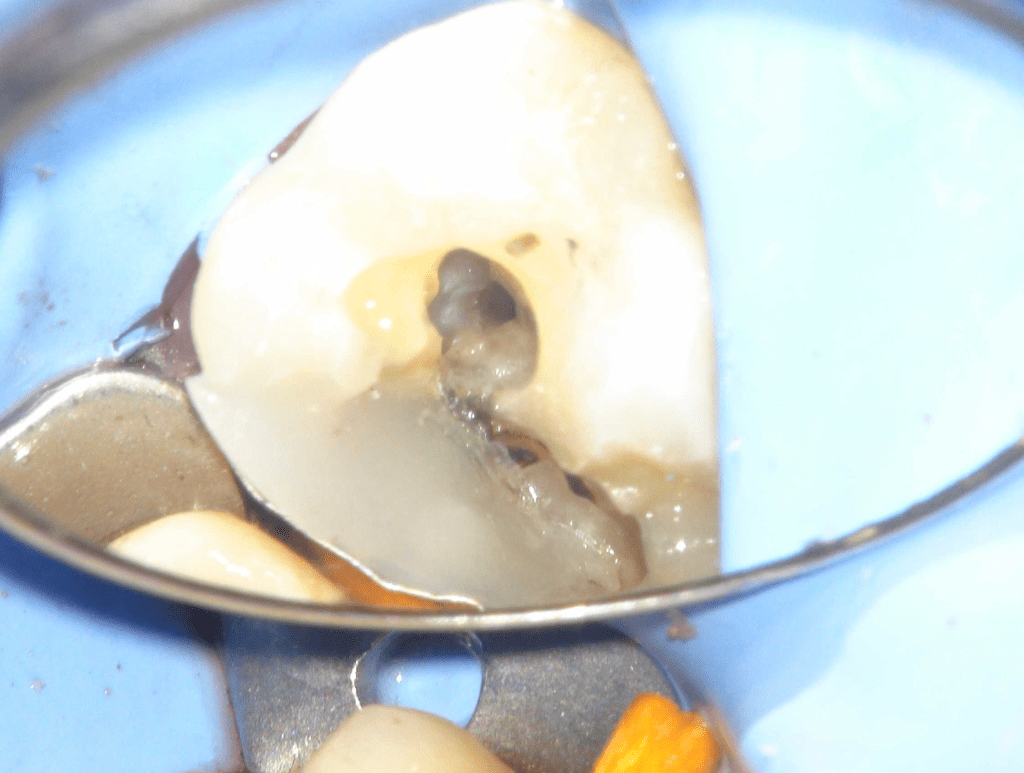

Reconstrucción preendodóntica

Reco pared vesticular